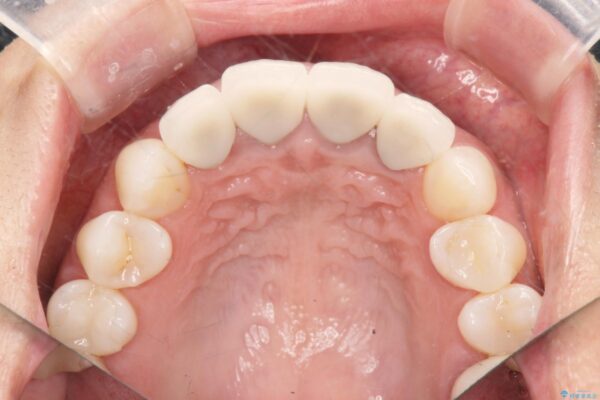

治療前

歯槽堤保存術を併用したブリッジ治療 治療前画像 歯槽堤保存術を併用したブリッジ治療 治療前画像 歯槽堤保存術を併用したブリッジ治療 治療前画像 歯槽堤保存術を併用したブリッジ治療 治療前画像 歯槽堤保存術を併用したブリッジ治療 治療前画像 歯槽堤保存術を併用したブリッジ治療 治療前画像 歯槽堤保存術を併用したブリッジ治療 治療前画像 歯槽堤保存術を併用したブリッジ治療 治療前画像 歯槽堤保存術を併用したブリッジ治療 治療前画像 歯槽堤保存術を併用したブリッジ治療 治療前画像